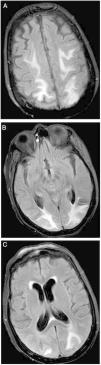

Presentamos el caso de un síndrome de encefalopatía posterior reversible secundario a afectación renal como forma de debut de una amiloidosis AL.

We present the case of a reversible posterior encephalopathy syndrome secondary to renal involvement as a debut form of AL amyloidosis.